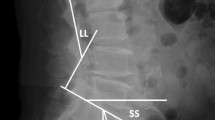

The method of measuring the height of the intervertebral disc space was as follows: On a lateral X-ray film, to measure the distance between the posterior edge of dislocated vertebra and the upper vertebral lamina of the lower vertebra, and that between the anterior edge of the lower vertebra and lower lamina of the dislocated vertebra. The average of these two value represented the height of the intervertebral disc space. And the difference between the heights of the intervertebral disc space before surgery and at the last follow-up was considered as the value for loss of the intervertebral disc space height.

The VAS and ODI scores were changed from 7.06 ± 2.67 points and 24.57 ± 10.63% preoperatively to 1.73 ± 0.81 points and 55.12 ± 28% at the last follow-up. Pain and dysfunction were improved in patients (VAS, p = 0.015, ODI, p = 0.003). The fusion rate of bone graft was 100%, and screw loosening was not observed. The intervertebral disc space height was 7.8 ± 3.7 mm before surgery, 10.1 ± 2.3 mm after surgery and 9.7 ± 1.2 mm at the last follow-up. This value was significantly increased after surgery compared with before surgery(p = 0.036). And the intervertebral disc space height was reduced by 0.4 ± 1.1 mm at the last follow-up compared with after surgery. There was no significant difference between these two periods (p = 0.62). The results are shown in Table 2 and the typical cases are shown in Figs. 2 and 3.